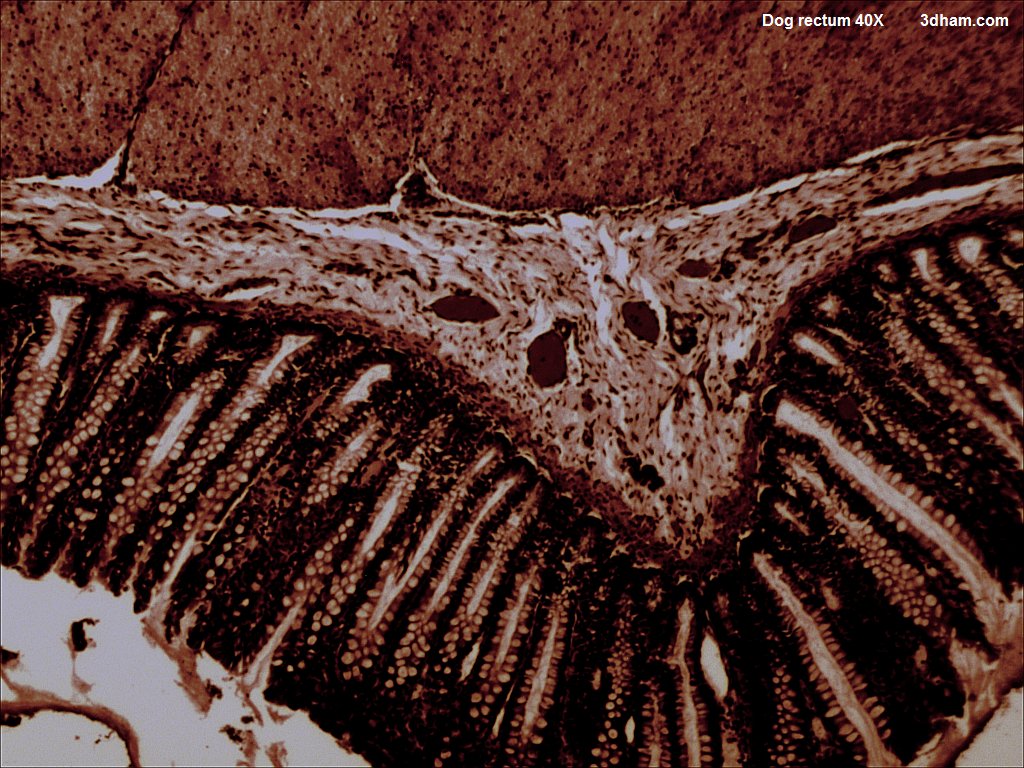

직장 벽은 위장관 벽과 유사하게 점막, 점막하층, 근육층, 장막(또는 외막)의 4개 층으로 구성된다.[5] 점막은 점액을 분비하는 술잔 세포가 풍부한 원주 모양 세포의 단일층으로 덮여 있다.[5] 이 점막은 고유층 위에 있으며, 점막근층이라고 하는 매끄러운 근육층이 있다.[5] 직장 점막에는 위장관의 다른 부분보다 술잔 세포의 농도가 더 높다.[5]

점막하층은 결합 조직으로 이루어져 있으며, 그 위에는 내측 원형 띠와 외측 세로 띠의 두 개의 근육 띠로 구성된 고유근층이 있다.[5]

직장과 항문이 만나는 선에서 내벽은 급격하게 변화한다. 이 선을 기준으로 내벽은 직장의 원주 모양 세포에서 여러 층의 평평한 세포로 바뀐다.[5]